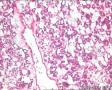

性别

男

年龄

63

临床诊断

结肿

一般病史

颈前肿物1周

标本名称

甲状腺

大体所见

肿物包膜完整,切面灰红灰黄质脆细腻

滤泡性腺瘤